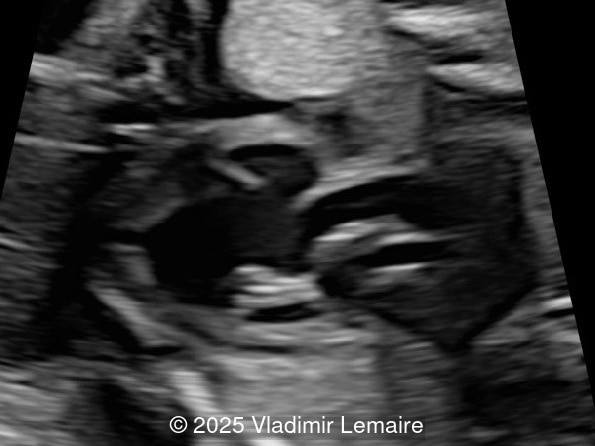

Left Ventricular outflow tract view.

Image 3 Left Ventricular outflow tract view.

Image 4 Left ventricular outflow tract view.

The size of the great vessel arising from the right ventricle should be evaluated for the presence of stenosis, which is a common association. The severity of right outflow tract obstruction directly correlates with the size of the right ventricle and the ventricular septal defect. Occasionally, pulmonary or aortic atresia can be found.